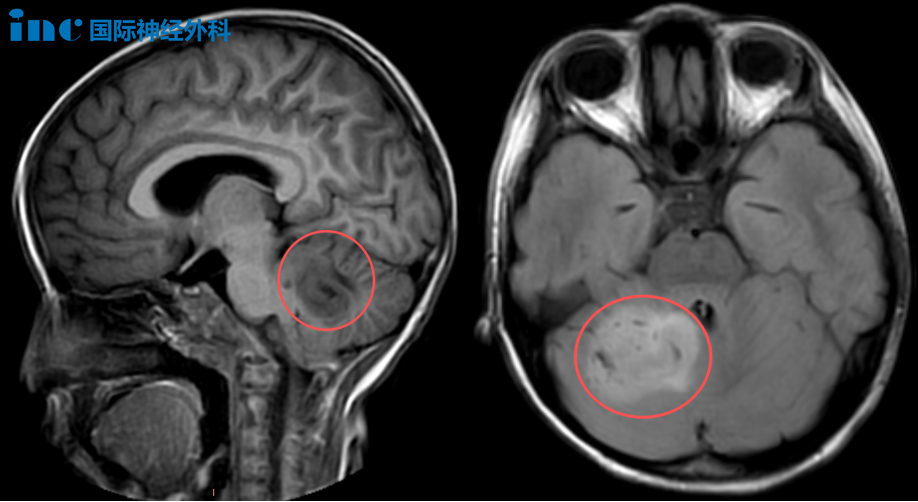

北京時間2025年10月20日,INC巴特朗菲教授于蘇州大學附屬兒童醫(yī)院順利完成一臺兒童腦瘤示范手術。

6歲女孩樂樂,在1個多月前被查出小腦占位,一度令樂樂一家陷入前所未有的迷茫和無助中。核磁上巨大的腫瘤,讓原本活潑開朗的女兒變得頭暈頭痛、嗜睡……而導致這一切的罪魁禍首卻一直得不到解決,這對樂樂父母來說,每一天都是煎熬。

幸而,就在一個多月后的今天,樂樂等來了巴教授。“手術對我來說并非難事,我能做到!”正如巴教授在術前評估的那樣,今日上午,巴教授主刀,在與蘇州大學附屬兒童醫(yī)院神外團隊的默契配合下,應用術中導航及術中超聲,仔細確認腫瘤邊界,最終為樂樂順利手術!

一個個好消息傳來,樂樂的手術不僅十分順利,還獲得了非常滿意的手術切除!眾人都為這個幸運的小女孩捏了一把汗,對于樂樂家人來說,盡管醫(yī)院外是一片陰天,但他們心中的暖陽正悄然升起。